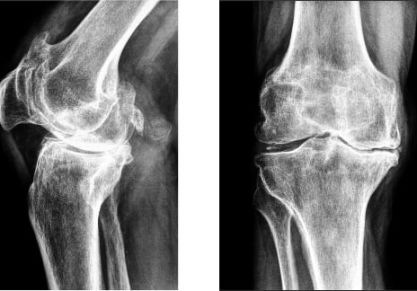

Артроз — это одно из самых опасных поражений сочленений, которое без надлежащей терапии может привести к деформации, а также дисфункции сочленений. Болезнь имеет дегенеративно-дистрофический характер. В основном поражается именно хрящевая ткань, которая отвечает за амортизационные свойства суставов.

Характеризуется патология сильными болевыми ощущениями, ограничением подвижности человека, а также изменением самого сочленения (часто не обратимым). Существуют такие виды заболевания:

• Гонартроз — артроз коленного сустава. Чаще всего он встречается после 45 лет, хотя в последнее время заболевание «молодеет».